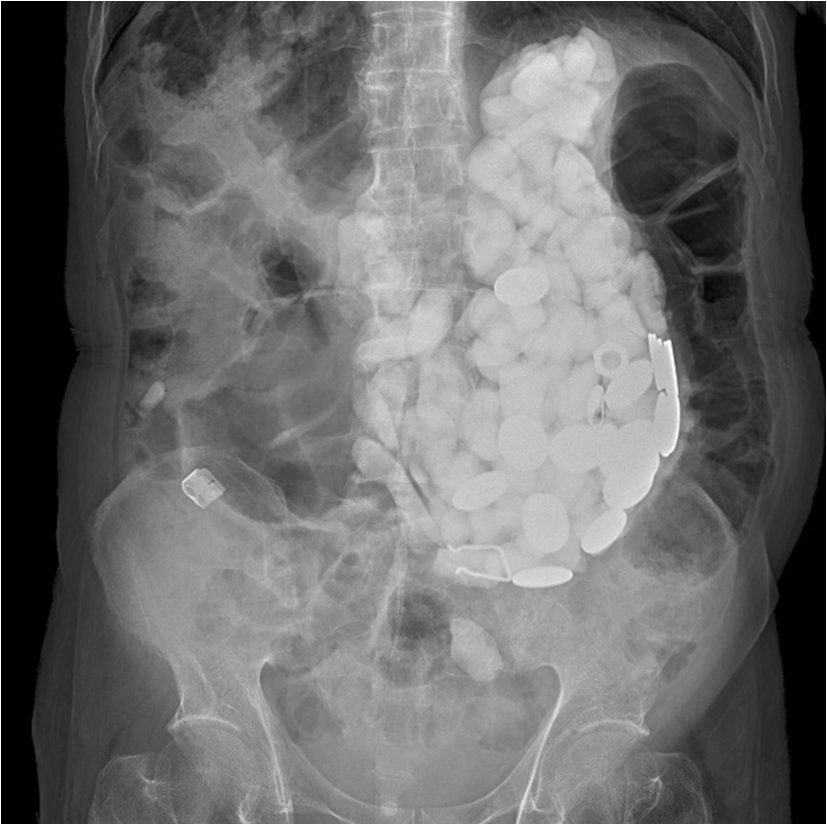

El caso ocurrido en Corea del Sur fue documentado en el Journal of Medical Case Reports. El médico cirujano Pyong Wha Choi narró que su equipo de cirujanos tuvo que extraerle del estómago a un hombre un total de dos kilos en piedras, tapas de botellas y monedas.

Según relató Wha Choi, en un inició se intentó extraer los objetos mediante una gastroscopía, con la cual se introduce un tubo delgado en el estómago a través de la boca. Debido a que el procedimiento falló por la cantidad de metales presentes en el estómago, fue hasta el día siguiente cuando se realizó una cirugía para retirar una a una las piedras, tapas y monedas.

"La cirugía era inevitable, había demasiados cuerpos extraños para extraer mediante endoscopia”, dijo el especialista a la revista.

“En el presente caso, a pesar de que el paciente no tuvo vómitos, la gran cantidad de piedras y monedas en su estómago le causaron dolor abdominal severo”, detalló Choi.